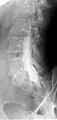

![]() Myelogram showing arachnoiditis in the lumbar spine. | |